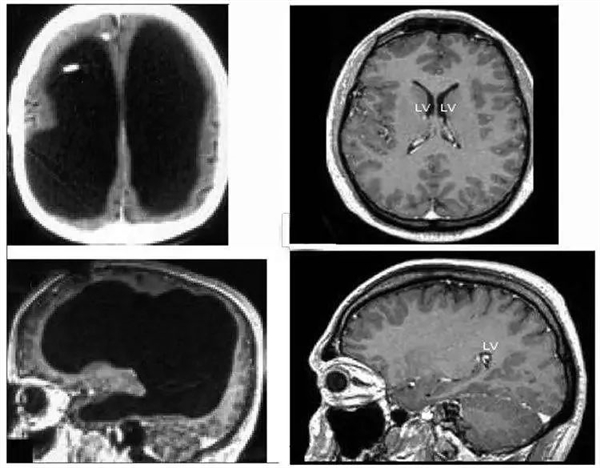

掃描的結(jié)果令所有人大吃一驚。他的大腦中央是一灘巨大的積水,腦子被擠壓到了邊緣薄薄一層。當(dāng)然嚴(yán)格來說這也不是純水,而是腦脊液。正常人腦子內(nèi)有少量的腦脊液,不斷產(chǎn)生又不斷排出到循環(huán)系統(tǒng)里,保持總量穩(wěn)定,但這位患者腦內(nèi)的排水系統(tǒng)發(fā)生了障礙,進(jìn)多出少,導(dǎo)致液體越積越多。

左邊為這名法國男子的大腦,中間黑色部分都是腦脊液;右邊為正常人的大腦